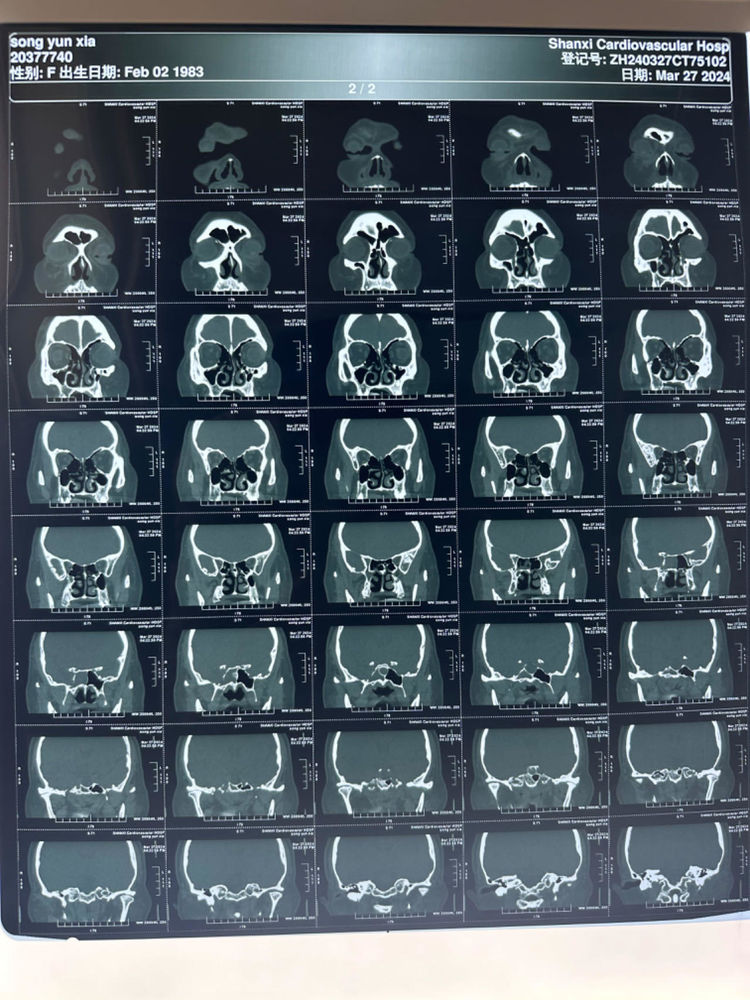

医院动态近期,维多利亚网络平台网址收治了一位特殊的病患。主因“右侧鼻腔间断流清水样涕1月余,加重2日”就诊于我院耳鼻喉头颈外科门诊,曾按鼻窦炎进行治疗,效果欠佳,张浩杰主任询问病史及检查后诊断为脑脊液鼻漏。

经核磁室、CT室、检验科及神经外科多学科协作讨论后,诊断为:右侧蝶窦外侧隐窝脑脊液鼻漏伴脑膜脑膨出。遂迅速制定详细手术方案,并顺利完成了内镜经鼻右侧蝶窦外侧隐窝脑脊液鼻漏修补术+股外侧筋膜部分切除术。